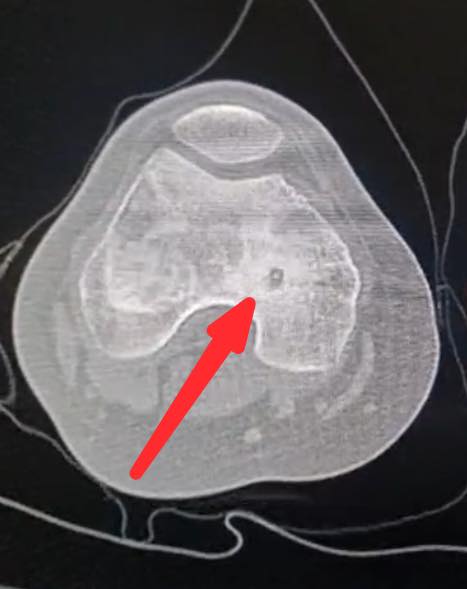

السوسنة - اجرى الكادر الطبي في مستشفى الأميرة بسمة عملية نوعية دقيقة لعلاج ورم عظمي حميد من نوع (Osteoid Osteoma) باستخدام تقنية الكي بالتردد الحراري (Radiofrequency Ablation) الموجهة بالأشعة المقطعية.

وبين الفريق الطبي أن خصوصية هذه الحالة تكمن في عمر المريضة (14 عاماً) حيث استقر الورم مباشرة على صفيحة النمو (Growth Plate) في عظم الفخذ البعيد. وتعتبر هذه المنطقة من الحساسية بمكان إذ ان أي خطأ قد يؤثر على النمو المستقبلي للعظم ما جعل استخدام تقنية الكي الحراري تحديا كبيرا يتطلب دقة فائقة لتجنب إلحاق أي ضرر حراري بالأنسجة المحيطة.